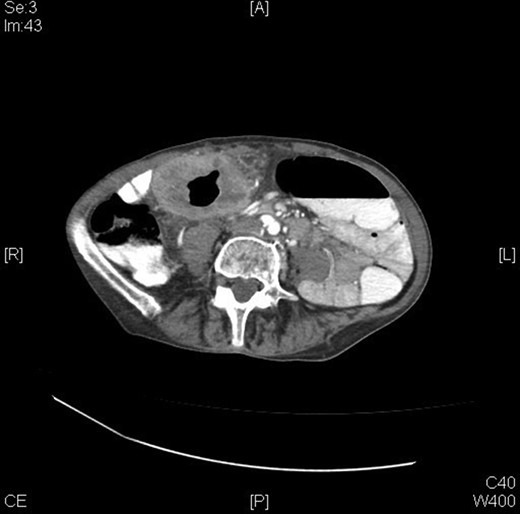

A 70-year-old female presented to the emergency department with complaints of diarrhea, vague, dull abdominal pain, unintentional weight loss and poor appetite. No hematochezia or melaena stated. Fecal occult is strongly positive in the ED. No endoscopies were found in her records. PMHx included COPD, osteoarthritis and DVT. Significant physical exam findings included mild, diffuse abdominal tenderness and RUQ palpable mass, and normal bowel sounds. Labs were significant for a hemoglobin of 5.7, hematocrit of 18.6% and CEA of 29.6. An abdominal/pelvis CT exhibited a 6 cm circumferential mass of the hepatic flexure (Figs 1–3). Two days later, a right hemicolectomy with en bloc pancreaticoduodenectomy was performed. Pathology showed adenocarcinoma stage IIIc (Figs 4–10). Post-operatively, an abdominal/pelvis CT showed bilateral pulmonary emboli and a 14 cm pelvic abscess. Bilateral lower extremity ultrasound showed low probability for DVT. Exploratory laparotomy was performed where the pelvic abscess was seen and extensive lysis of adhesions, resection of ileocolonic anastomosis for contained leak and ileostomy performed. Approximately 4 months after discharge, the patient passed away while in a long-term care facility.

A 2013 study showed that patients who are appropriate for right hemicolectomy with en bloc pancreaticoduodenectomy have the following characteristics: ‘(i) no distant metastasis, (ii) R0 resection being possible on the basis of the preoperative examination, (iii) the patient’s condition being good enough to accept radical multivisceral resection and (iv) the surgical team being experienced enough to perform the procedure’ [10]. Preoperative evaluations are strongly recommended to ensure that patients qualify. Preoperative staging is also a key factor; this is done through abdominal CT scans. CT scans have a significant (99%) ability to detect liver metastases, moderate ability to reveal cT4 stage (86%) cancers but are poor at detecting peritoneal carcinomatosis [10]. CTs are able to distinguish colonic tumor stages pre-operatively and can show invasion through the muscularis propria, indicating stage T3/T4 [10].